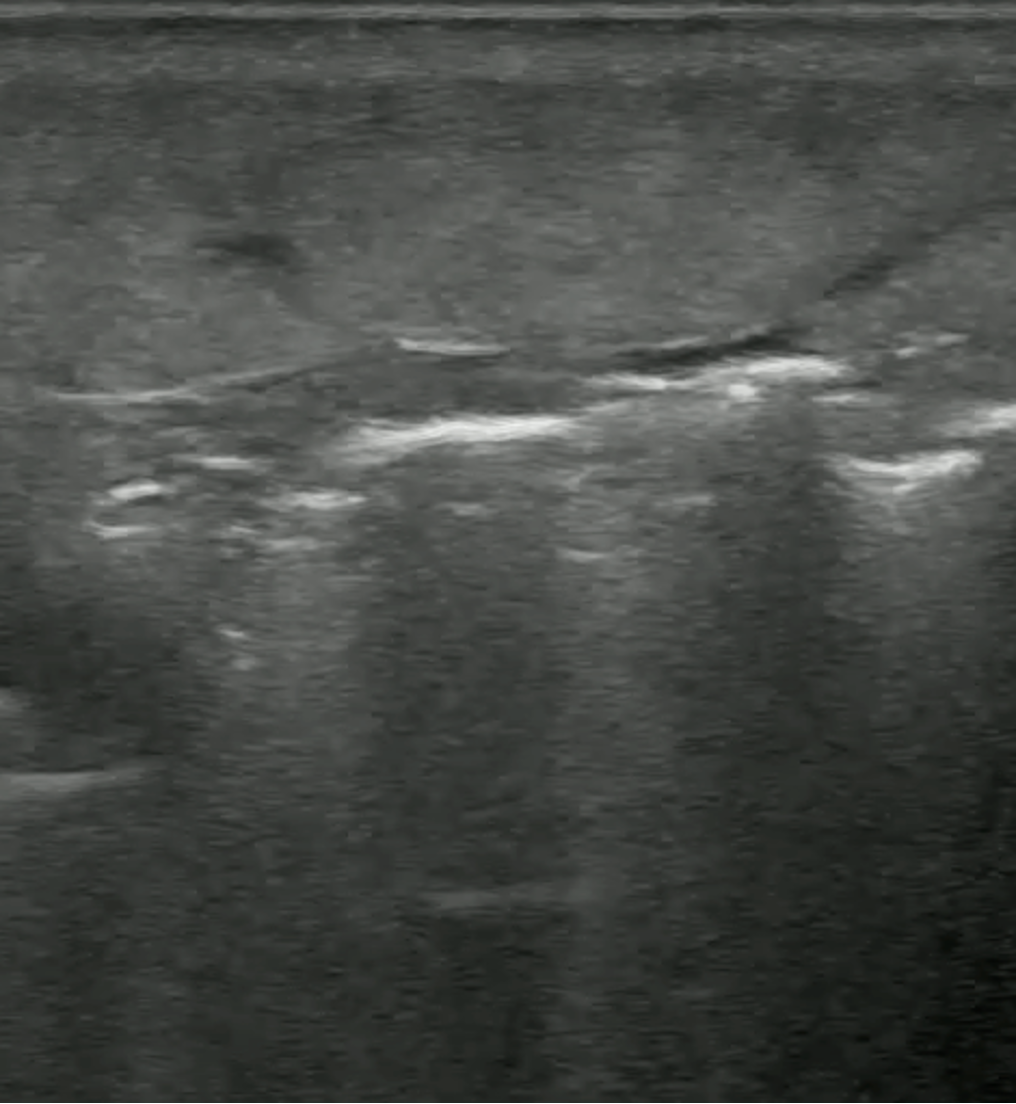

POCUS Images

• Medial Thigh Soft Tissue

POCUS Interpretation

• Cobblestoning: Fat lobules separated by hypoechoic fluid (Blue arrows)

• Seen in any cause of tissue edema

cobbllstoning

• Hyperechoic lines (Red Arrow) with dirty white shadowing (Green Arrows)

• This Finding is suggestive of gas within the Soft Tissues

hyperechoiclines

• Fluid Stripe along Fascial Plane

fluid stripe